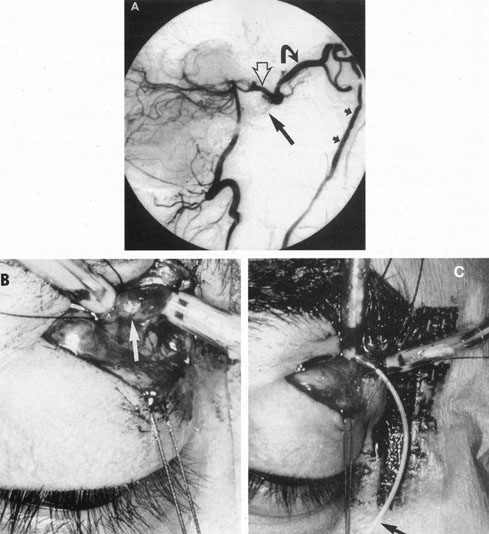

From 85% to 90% of AVMs are in the supratentorial compartment and are supplied primarily by the carotid circulation (Figs. 7 and 8). The remainder are supplied by the vertebrobasilar system. The approximate frequency of location is as follows: frontal, 22%; temporal, 18%; parietal, 27%; occipital, 5%; and deep intraventricular or paraventricular, 18%. The intracerebral site of the malformation does not necessarily indicate that there will be signs referable to that area simply from the mass effect of the malformation. Clinical features primarily result from subarachnoid hemorrhage or intraparenchymal hemorrhage with hematoma formation.

Fig. 7. Supratentorial arteriovenous malformation in a 28-year-old woman with a history of focal motor seizures for many years and a recent subarachnoid hemorrhage. A: Lateral projection carotid arteriogram demonstrating a huge deep hemispheral arteriovenous malformation. B: Frontal projection. C: Fundus photograph showing anomalous tortuous vasculature in each eye. No retinal arteriovenous shunt was detectable.

Fig. 8. Multiple supratentorial arteriovenous malformations (AVMs). A: Lateral projection of left carotid arteriogram shows dilated afferent artery (solid arrow) feeding the right hemispheric parietal AVM (open arrow). B: Right carotid injection fills a second, more posteriorly located, parietooccipital AVM (open arrow), which drains immediately to markedly dilated cortical veins (curved arrow).